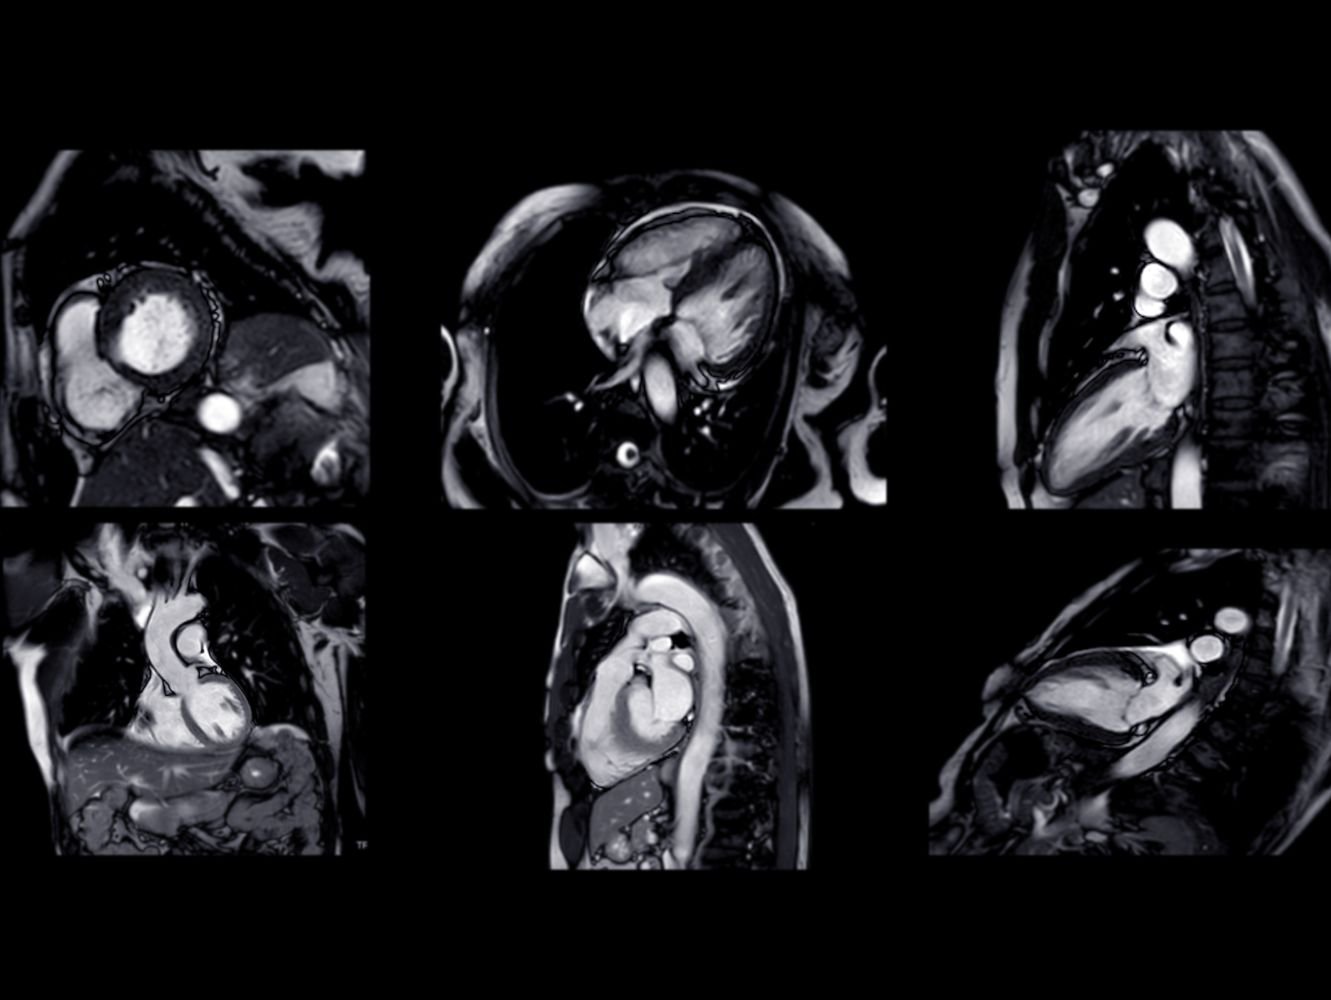

A Cardiac MRI (Magnetic Resonance Imaging) scan provides highly detailed images of the heart and surrounding blood vessels. Unlike traditional imaging techniques such as X-rays or CT scans, an MRI uses powerful magnetic fields and radio waves to create clear, high-resolution images of soft tissues. This allows healthcare professionals to examine the heart’s structure and function in unprecedented detail, without exposing patients to dangerous radiation.

This technology offers a unique view into the heart’s condition, including its muscles, valves, contractions and blood flow, providing crucial information that can guide the diagnosis and treatment of various cardiac conditions. This makes MRI particularly valuable for heart conditions, where detailed imaging is essential for early diagnosis and monitoring.

- Detailed Imaging: Cardiac MRI produces exceptionally clear images of the heart and blood vessels, making it one of the most precise imaging methods available. It can detect the smallest changes in the structure and function of the heart, which may be missed by other imaging techniques.